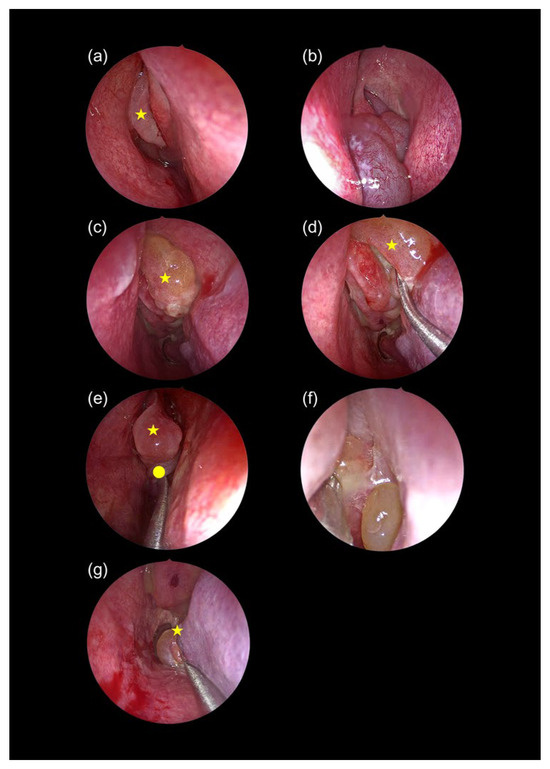

16 pages, 1722 KB

A Clinically Relevant Classification and Staging System for Chronic Rhinosinusitis with Nasal Polyposis: A Cross-Sectional Study

Diagnostics 2025, 15(24), 3197; https://doi.org/10.3390/diagnostics15243197 - 14 Dec 2025

Background/Objectives: Tissue eosinophilia plays a central role in chronic rhinosinusitis with nasal polyposis (CRSwNP), yet the spectrum of disease, particularly central compartment atopic disease (CCAD), remains underexplored. This study aimed to classify CRSwNP into three distinct phenotypes, eosinophilic CRSwNP (ECRSwNP), non-eosinophilic CRSwNP (NECRSwNP), [...] Read more.

Background/Objectives: Tissue eosinophilia plays a central role in chronic rhinosinusitis with nasal polyposis (CRSwNP), yet the spectrum of disease, particularly central compartment atopic disease (CCAD), remains underexplored. This study aimed to classify CRSwNP into three distinct phenotypes, eosinophilic CRSwNP (ECRSwNP), non-eosinophilic CRSwNP (NECRSwNP), and CCAD, based on radiologic and endoscopic features. It also proposes a novel severity-based staging system to guide clinical decision-making. Methods: A cross-sectional observational study was conducted in a single private clinic between January 2019 and August 2025. Patients were assessed using clinical history, paranasal sinus computed tomography (CT), and intranasal endoscopy. Key variables included symptom clusters, comorbidities, hematologic and atopy profiles, radiologic and endoscopic findings, histopathology, and pre-treatment SNOT-22 scores. Results: A total of 2060 patients (mean age: 29.8 ± 11 years; 51.8% male) were included. Asthma was the most frequent comorbidity (23.5%). Classification into ECRSwNP, NECRSwNP, and CCAD was achieved using integrated clinical, radiologic, and histopathologic criteria. Conclusions: This study presents a phenotype- and severity-based classification system for CRSwNP that incorporates endoscopic and radiologic features. This framework may enhance diagnostic accuracy and enable more tailored therapeutic strategies. Full article

Show Figures

Figure 1